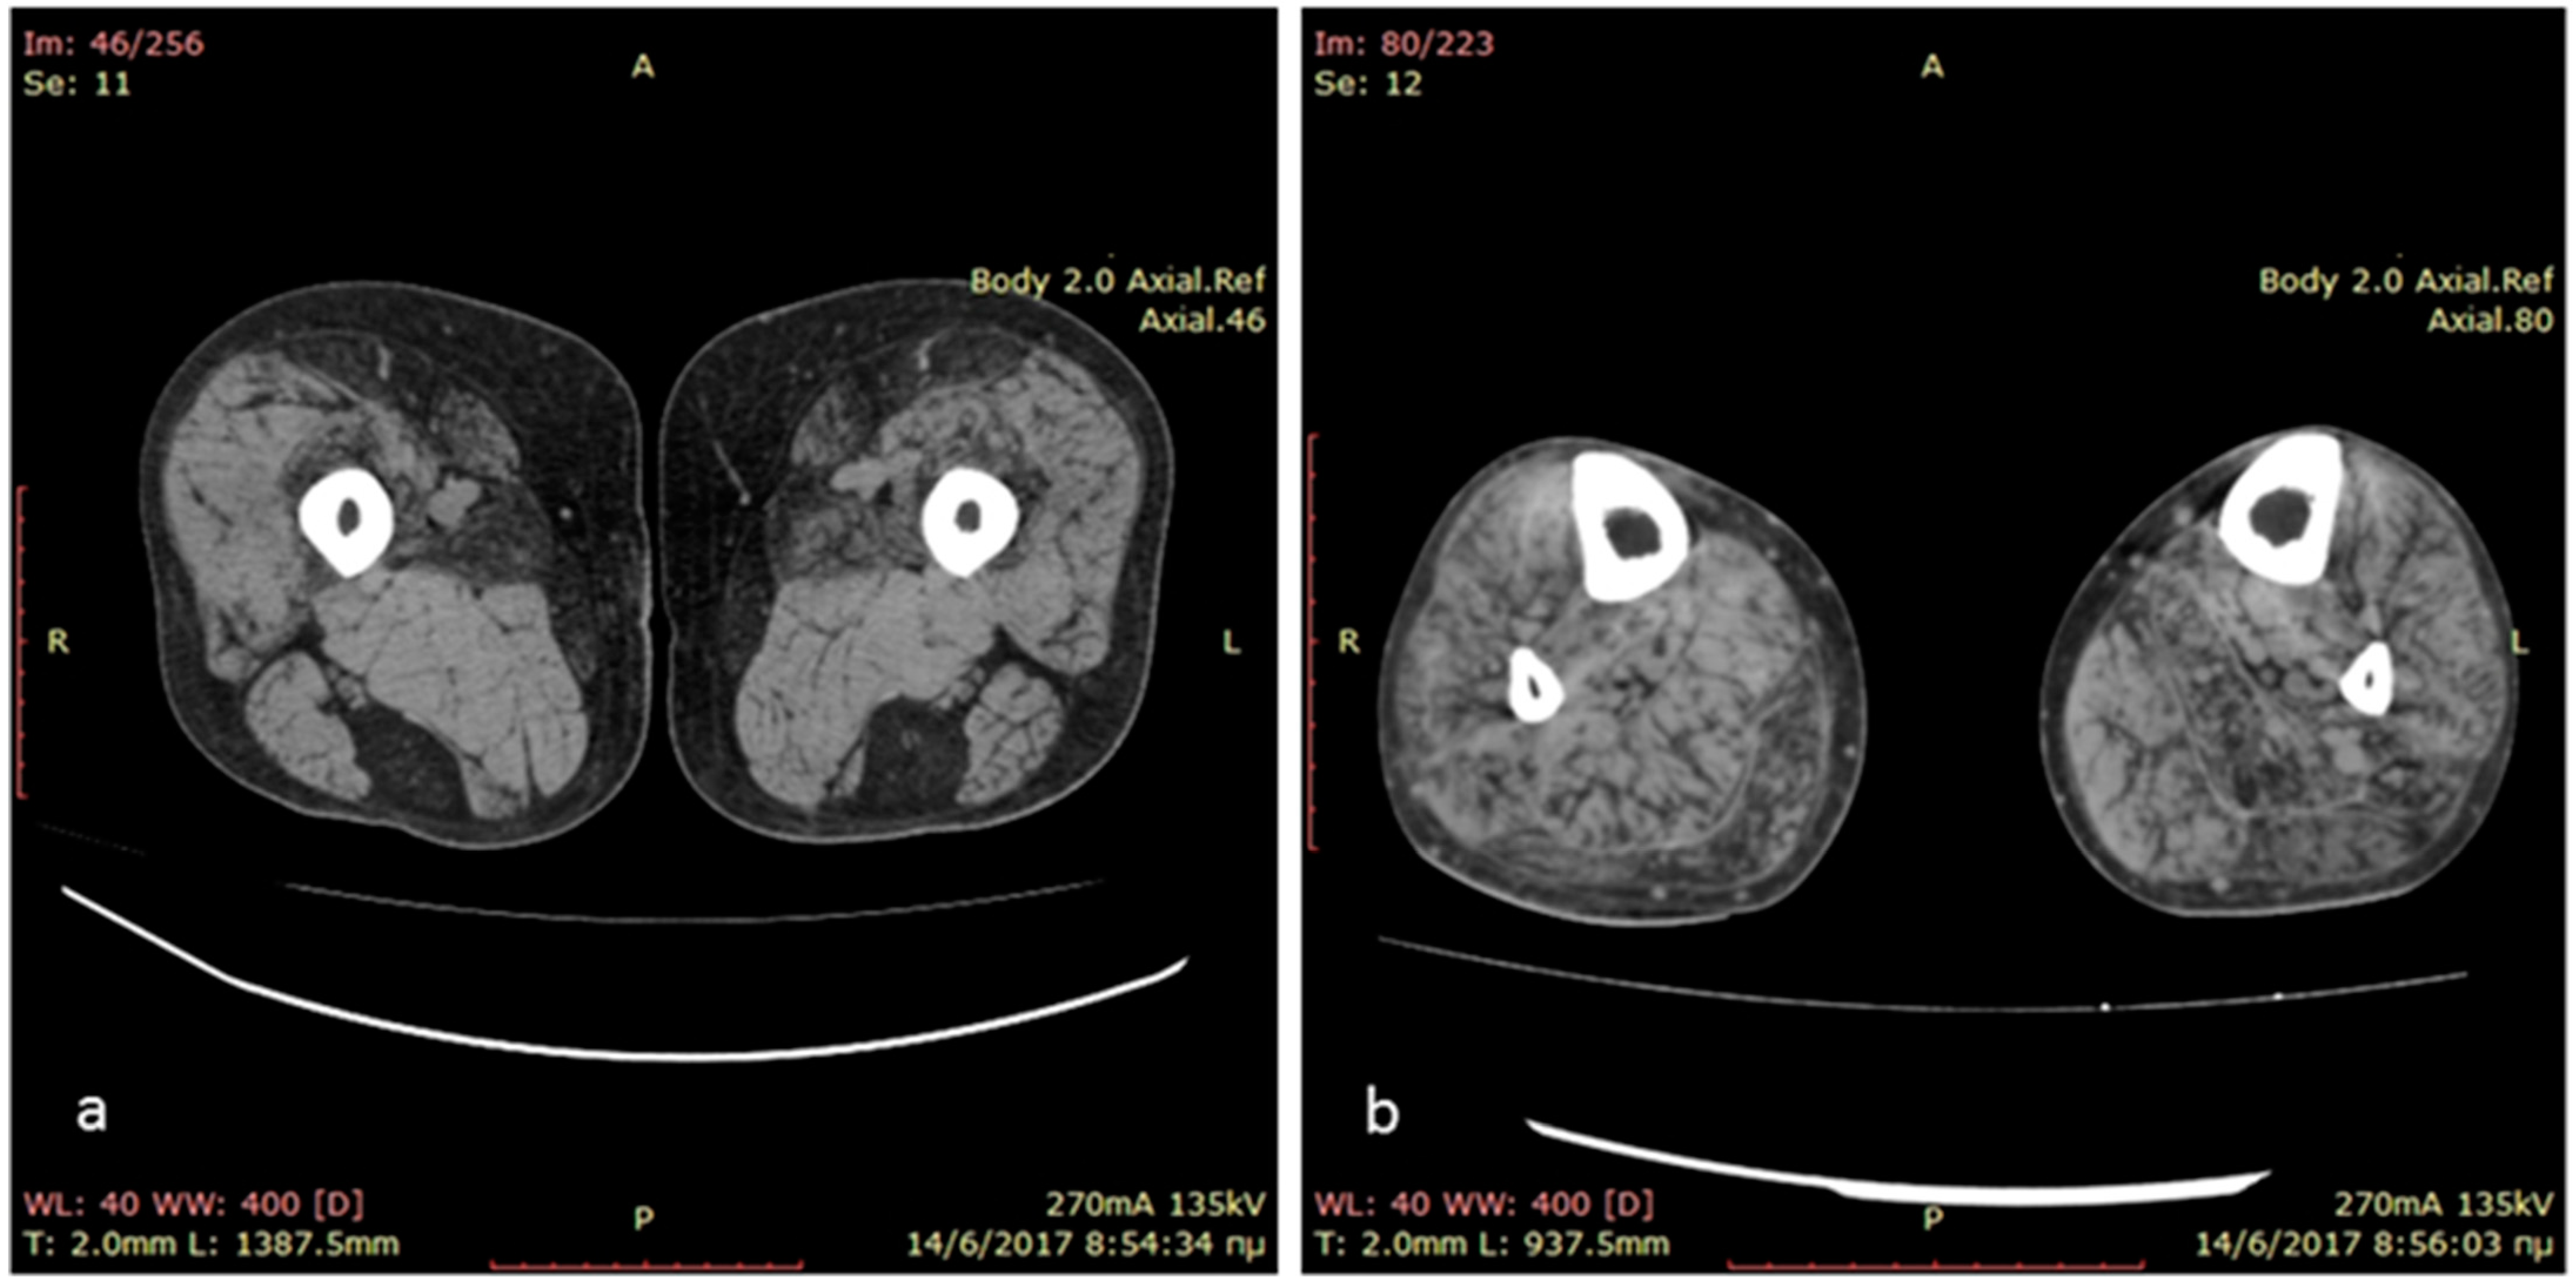

The index case is a 36-year-old man born at term, following an uneventful pregnancy and a normal delivery, to non-consanguineous healthy parents. His psychomotor development was normal and he reported being athletic as a child. At the age of 18 years, during his military service, the patient was diagnosed with restrictive hypertrophic cardiomyopathy and a year later a pacemaker was implanted due to syncopal episodes. At the age of 23 years, he was diagnosed with atrial fibrillation complicated by an ischemic stroke with no residual neurologic deficit. Since the age of 28 years, he has reported difficulties climbing stairs and getting up from a squat. He was firstly seen at the neuromuscular clinic at the age of 33 years, and he presented bilateral scapula alata, and a waddling and stepping gait. There was mild weakness in the upper limbs (biceps and finger extensor muscles graded 4/5 on the MRC scale) and more severe in the lower limbs (hip extensors and psoas muscles 1/5 on the MRC scale, hip abductors, biceps femoris 3/5 on the MRC scale). Distally, there was involvement of tibialis anterior and peronei muscles (3/5 on the MRC scale). His serum creatine kinase levels were mildly elevated at 400 UI/L (normal values < 180 U/L). Needle electromyography demonstrated small amplitude, short duration, polyphasic motor unit action potentials, with early recruitment and small amounts of fibrillation potentials and positive sharp waves, as well as myotonic discharges in all examined muscles. A lower limb muscle computed tomography revealed fatty degeneration of semitendinosus, gracilis, sartorius and adductor longus muscles in the thigh and diffuse fatty degeneration of leg muscles (Figure 1).

Figure 1.

Muscle computed tomography of the thighs showing predominant involvement of semitendinosus, gracilis, sartorius and adductor longus muscles in the thighs (a) and diffuse fatty degeneration of leg muscles (b).

In the framework for his muscle disease, the patient underwent lower limb computed tomography showing predominant involvement of semitendinosus, gracilis, sartorius and adductor longus muscles in the thigh and diffuse fatty degeneration of leg muscles. Muscle imaging has become an integrated part of the diagnostic workup of myopathies, and the recognized pattern of muscle involvement often points to the underlying gene defect [32]. The involvement of sartorius and gracilis, as opposed to most muscular dystrophies and the pronounced selective fatty infiltration in semitendinosus, sartorius and gracilis in the thighs and peroneal muscles at the calf level, are highly suggestive of a desminopathy, irrespective of the underlying mutation, disease stage or clinical muscle involvement [33].